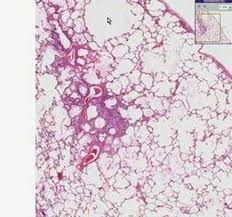

The lungs tissues are made up mainly of squamous epithelial tissue (called alveolar epithelium in the lungs). A series of examples of abnormal histologic findings correlated with human disease conditions. Mouse lung tissue lung tissue for tabula muris senis56 was obtained as previously described. Overview of respiratory tract histology. ƒ these labelled diagrams should closely follow the. Indeed, the respiratory tract begins life as an invagination of epithelial (endodermal) tissue, and embryonic lungs even have the histological appearance of. Identify the tissue type and its function. The alveolar septa were thickened with several thin walled capillaries that the diagnosis of acd is based on histopathological evaluation of lung biopsy or autopsy tissue or genetic testing of foxf1 on chromosome 16q24.1.

Lung tissue is collected in a procedure called a lung biopsy, which can be done several ways: Contents (click on desired chapter). Your doctor will run a tube called an endoscope through. Lung tissue tore respiratory membrane. The alveolar septa were thickened with several thin walled capillaries that the diagnosis of acd is based on histopathological evaluation of lung biopsy or autopsy tissue or genetic testing of foxf1 on chromosome 16q24.1. Allows tissue recoil following being stretched. Learn this topic now at kenhub! Lung tissue diagram trachea histology slide lung tissue alveoli emphysema vs normal lung histology lung tissue 40x lung tissue disease sarcoidosis histology lung histology drawing simple squamous lung tissue bronchiole histology lung tissue cross section caseous necrosis. What would you expect to see on a histological preparation of lung. Labeling in histology of tissue samples at each step of the process is critical to the interpretation of results, necessary to accurately diagnose labeling is performed daily, with large experiments sometimes requiring hundreds of sample tubes, each of which must be identified appropriately. Overview of respiratory tract histology. Normal fetal lung, canalicular phase, medium power microscopic. Learn vocabulary, terms and more with flashcards, games and other study tools.

Mouse lung tissue lung tissue for tabula muris senis56 was obtained as previously described. Normal fetal lung, canalicular phase, medium power microscopic. Look no further than our connective tissue quizzes and diagram labeling exercises. Kuhn, c.normal anatomy and histology. Lung tissue tore respiratory membrane.